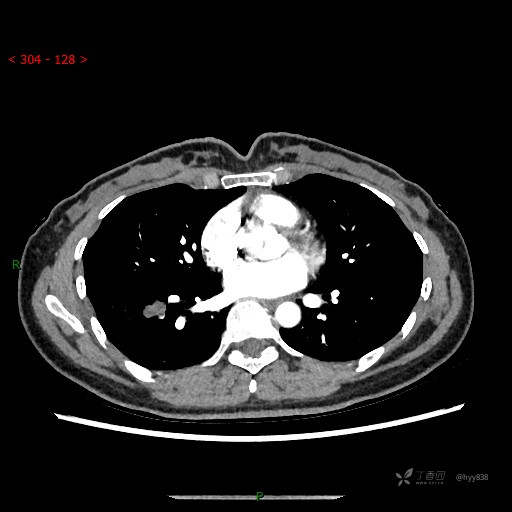

胸部CT平扫

增强动脉期